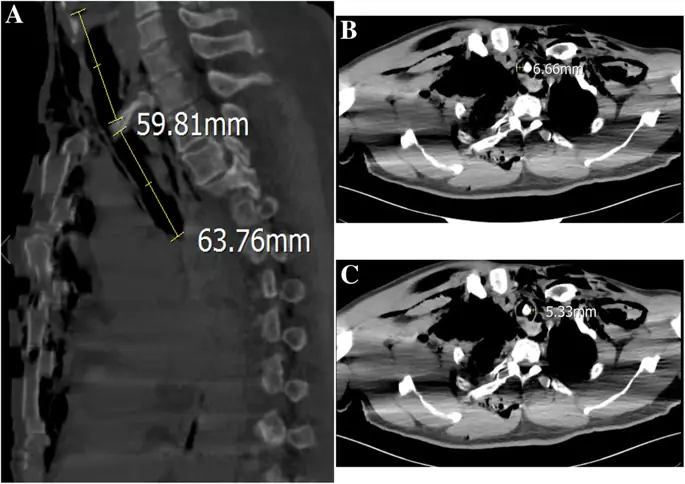

Рисунок 3

Предоперационная оценка трахеобронхиальных разрывов КТ высокого разрешения. сагиттальное КТ изображение грудной клетки с разрывом задней стенки трахеи до 59, 81 мм ниже голосовой щели и на 63, 76 мм над килем. b, c Аксиальная компьютерная томография грудной клетки, показывающая тень кости в трахее; самая большая остаточная полость трахеи слева составляла 5, 33 мм в диаметре и 6, 66 мм справа.

Письменное информированное согласие на публикацию данного дела было получено от пациента. Мужчина 56 лет (рост 165 см; вес 70 кг) без значительного медицинского анамнеза обратился в отделение неотложной помощи с жалобами на боль в правой груди, застой в груди и одышку после получения тупой травмы правой груди. Его жизненные показатели были следующими: частота сердечных сокращений (ЧСС), 91 уд / мин; частота дыхания (ОР), 34 вдоха / мин; артериальное давление (АД), 108/71 мм рт.ст.; и начальная пульсовая оксиметрия насыщения (SpO 2) 85%. Газ артериальной крови: рН 7, 35, ПаСО 2 47 мм рт. Ст. И ПаО 2 49 мм рт. Хрипящая грудь и парадоксальное дыхание были очевидны. Значительная подкожная эмфизема в области шеи и передней части груди была диагностирована с выраженным крепитацией. Компьютерная томография (КТ) показала массивную подкожную эмфизему, пневмомедиастинум, множественные переломы ребер, двусторонний гемопневмоторакс и компрессионный пневмоторакс (рис. 1 а и б). Было замечено смещение сочленения грудины, и стернальная часть правого первого ребра проникла через заднюю стенку трахеи над килем (рис. 2). Грудная трубка была вставлена для декомпрессии пневмотораксов и гемопневмоторакса, и проблемы с дыханием были облегчены. К сожалению, быстрое ухудшение подкожной эмфиземы указывало на постоянную утечку воздуха через разрыв через 3 часа. У пациента развился респираторный дистресс и он стал гемодинамически нестабильным. Эмерджентная КТ показала, что правое первое ребро проникло через заднюю стенку трахеи примерно на 6 см ниже голосовой щели и на 6 см выше киля (рис. 3а). Первое ребро разделило трахею на две части: 5, 3 мм в диаметре слева и 6, 6 мм справа (рис. 3, б и в). Пациент был быстро переведен в операционную. Он был взволнован, при дыхательной недостаточности и его жизненные показатели были: ЧСС 108 уд / мин; 30 вдохов в минуту; BP 90/58 мм рт.ст. и SpO 2 80%. Мы поддерживали гемодинамическую стабильность с помощью внутривенного фенилэфрина. Фиброоптический бронхоскоп был сразу же доступен с эндотрахеальными трубками разных размеров. Общая анестезия была индуцирована мидазоламом 2 мг, фентанилом 0, 05 мг и 2% ~ 5% севофлюраном при сохранении спонтанной вентиляции. Стерильный гибкий волоконно-оптический бронхоскоп, загруженный 5, 5 мм эндотрахеальной трубкой (наружный диаметр 7, 3 мм), идентифицировал разрыв трахеи, и эндотрахеальная трубка была продвинута дистально мимо места разрыва. Он самопроизвольно дышал с фракцией вдыхаемого кислорода 100%, дыхательным объемом 330 мл, частотой 30, SpO 2 95% и парциальным давлением конечного прилива двуокиси углерода (PetCO 2) 40 мм рт. Глубина анестезии поддерживалась до достижения показателя биспектрального индекса 40-60. Хирургическая бригада открыла грудную полость, чтобы обнажить правое первое ребро, а правое первое ребро было удалено примерно через 30 минут (рис. 4а). Эндотрахеальную трубку диаметром 7, 5 мм затем заменяли и располагали дистально до разрыва под руководством гибкой бронхоскопии. После подтверждения расположения эндотрахеальной трубки внутривенно вводили цисатракурий 14 мг и фентанил 0, 15 мг. Пациенту была проведена искусственная вентиляция легких с интервалом положительной вентиляции. Респираторные параметры были следующими: фракция вдыхаемого кислорода 60%, дыхательный объем 550 мл, частота 12, пиковое давление в дыхательных путях 22 см H 2 O, SpO 2 98% и PetCO 2 38 мм рт. Непосредственное хирургическое восстановление разрыва трахеи было успешным, и он был переведен в отделение интенсивной терапии. В отделении интенсивной терапии ему управляли на вентиляторе с синхронизированной прерывистой принудительной вентиляцией и постоянным положительным давлением в дыхательных путях. Для улучшения легочной функции на 5-й день после первой операции были выполнены плановые хирургические операции по восстановлению перелома грудины, множественных переломов ребер и гемопневмоторакса под общей анестезией, а у пациента был экстубирован на 7-й день после операции. Повторная КТ продемонстрировала целостность стенки трахеи (рис. 4 б). Комплексная реабилитация проводилась в течение 2 недель, и он был выписан домой в послеоперационный день 41.